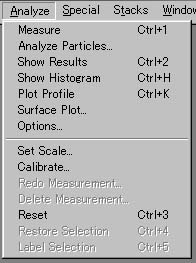

Scion Imageにおける画像解析は,メニュー「Analyze」から実行される(図5-1).ここでは,画像処理に関して有用と考えられる「Measure」,「Show Histogram」,「Plot Profile」,「Surface Plot」について説明する.

図5-1 画像解析メニュー「Analyze」